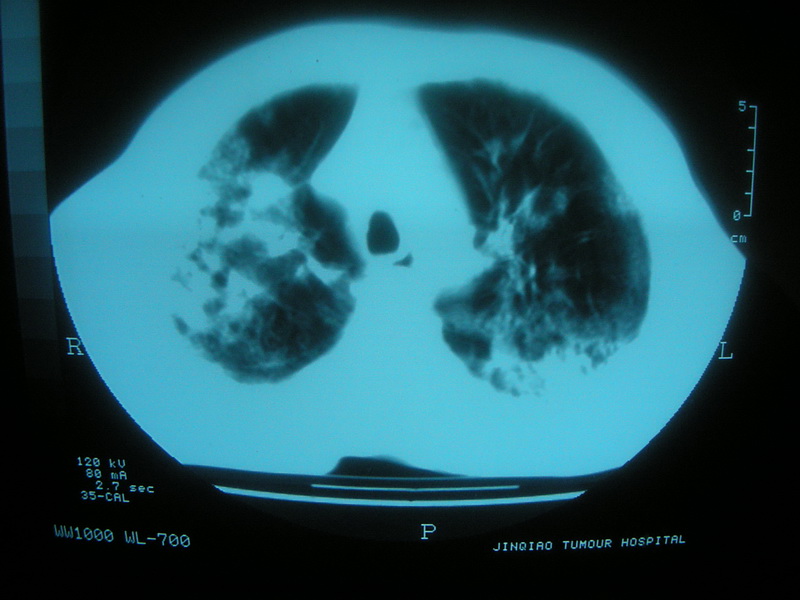

标题: CT11692:男,63岁,糖尿病史15年.抗炎治疗7天,病情 [打印本页]

标题: CT11692:男,63岁,糖尿病史15年.抗炎治疗7天,病情

请老师看看是结核还是炎症?

根据影像表现及临床符合结核感染。

双肺继发性肺结核伴感染!

双肺继发性肺结核伴支气管播散。